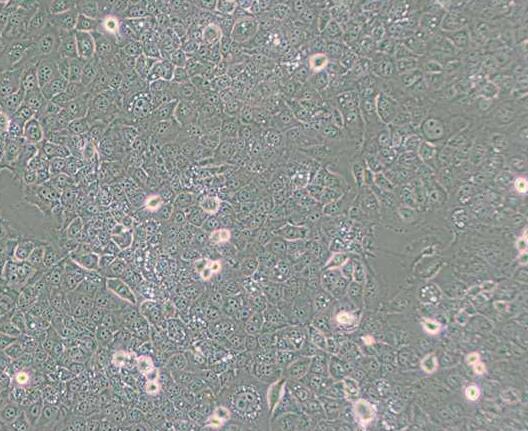

上皮细胞样,带有长的伪足

细胞形态 上皮细胞样,带有长的伪足